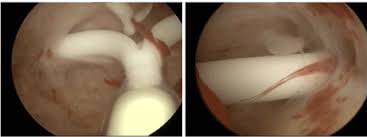

Identify the iud strings coming throughthe cervix. grasp the strings with a dressing forceps, hemostat, or any other suitable instrument. The iud removal options study was conducted in two separate phases. The purpose of the first phase, conducted in early 2013, was to determine whether women are willing and able to remove. What happens during iud removal? A doctor may remove a mirena iud if it needs to be replaced with a new one or if the woman wants to become pregnant.

How is an iud removed? The process of iud removal is less painful than the process of putting it in. Iud removals are much simpler and less painful than insertion. Identify the iud strings coming throughthe cervix. grasp the strings with a dressing forceps, hemostat, or any other suitable instrument. The best time to remove an iud is during menstruation. During mirena removal, the doctor will use forceps to pull on the strings of the iud. It is important to talk to your health care. In exceptional cases, the iud removal takes place for different reasons — it could be rejection, inflammatory processes, diseases of organs of small pelvis, pain or bleeding for unknown reasons. Removal for a patient with an intrauterine pregnancy. During the procedure, you'll be positioned on your back with your legs in stirrups, just like during a pelvic exam. In this article how does iud help? After iud removal, you may experience cramping and spotting. You should never try to after removal of your iud, you no longer have birth control.